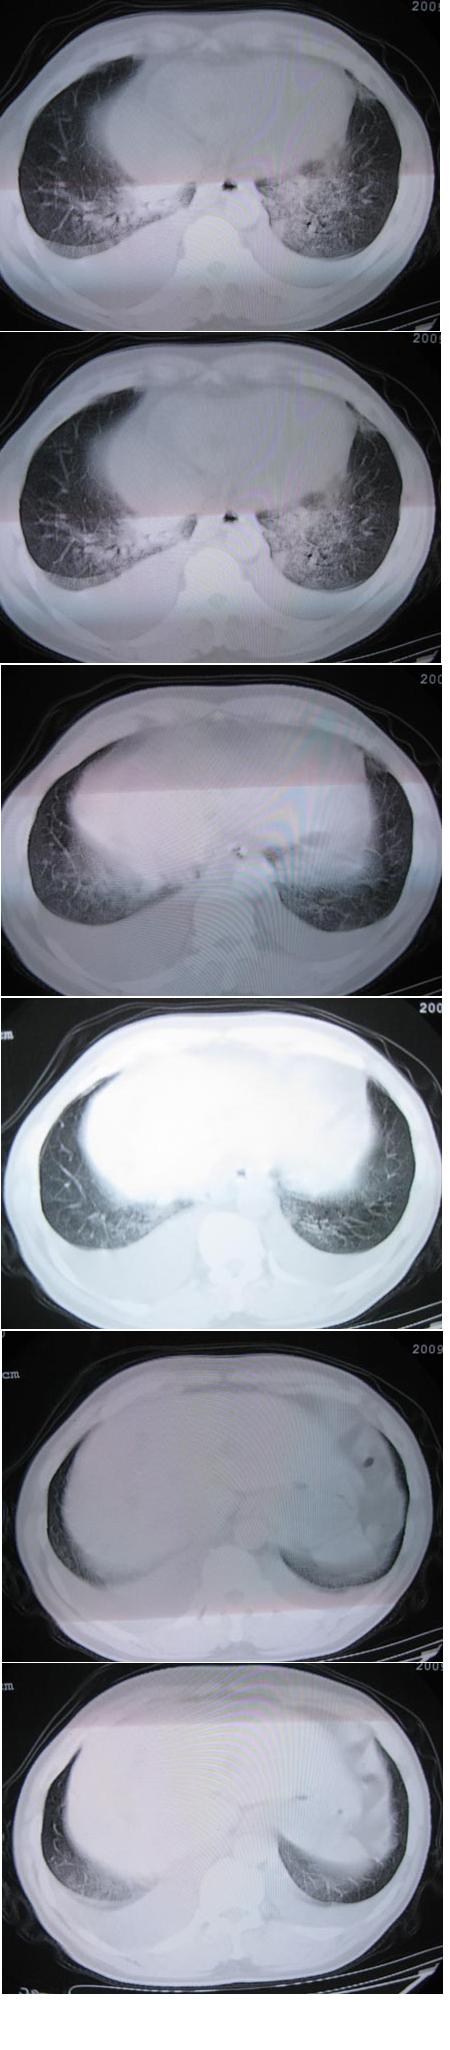

男,36岁,胸闷气喘三天来诊

典型肺泡性肺水肿伴双侧胸腔积液。

典型肺泡性肺水肿伴双侧胸腔积液,病因呢?

肺泡性肺水肿并双侧胸腔积液。

肺水肿,双侧胸水,不会差,要找以下原因。

支持 1)肺水肿。2)双侧胸腔积液。3)建议进一步检查,并更多的提供病情资料。